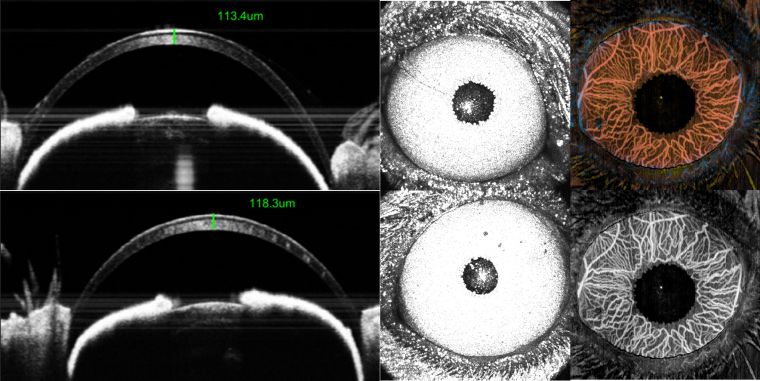

老鼠角膜形态结构变化

研究角膜新生血管、碱烧伤方向

可视化视网膜下腔注射隆起高度定量化,对应药物剂量对视网膜影响研究

基因治疗、干细胞治疗视网膜下腔注射---排除视网膜下腔物理损伤得影响